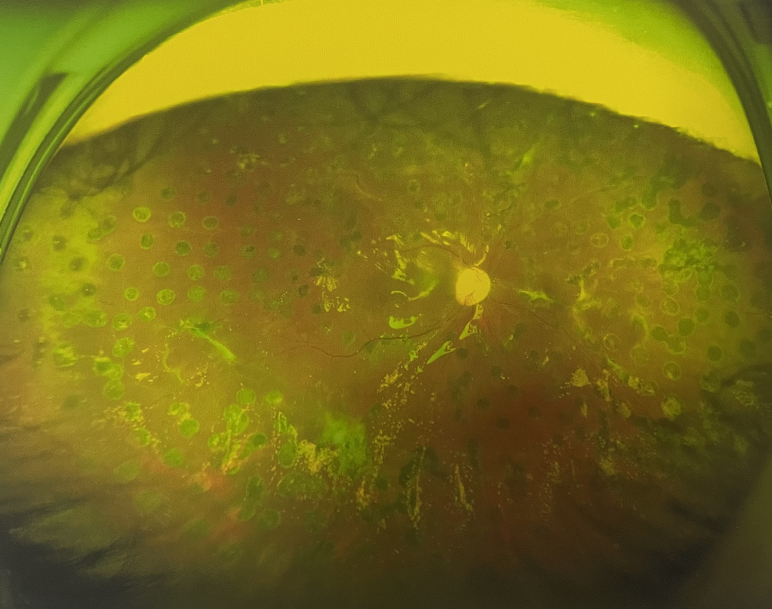

右眼術(shù)后

由于王女士的左眼沒有聽從醫(yī)生盡快做手術(shù)的建議,一直耽誤,從4月前的0.4視力逐漸下降到僅剩眼前手動,導(dǎo)致左眼發(fā)展到糖尿病視網(wǎng)膜病變VI期(屬于6期糖網(wǎng)中的晚期),已經(jīng)產(chǎn)生大量新生血管+纖維增值+廣泛牽拉性視網(wǎng)膜脫離,由于耽誤了病情,且病情發(fā)展異常迅速,導(dǎo)致目前左眼連保住眼球都很困難。

“而如果4月余前,左眼及時手術(shù)(當(dāng)時左眼病情比右眼輕,增殖膜還未累及黃斑),左眼將恢復(fù)的比右眼還好,甚至可以恢復(fù)到0.8或1.0,而現(xiàn)在連保住眼球的機(jī)會都很渺茫”,張小虎醫(yī)生表示實在可惜。

4個月前的左眼

左眼發(fā)展到糖尿病視網(wǎng)膜病變VI期